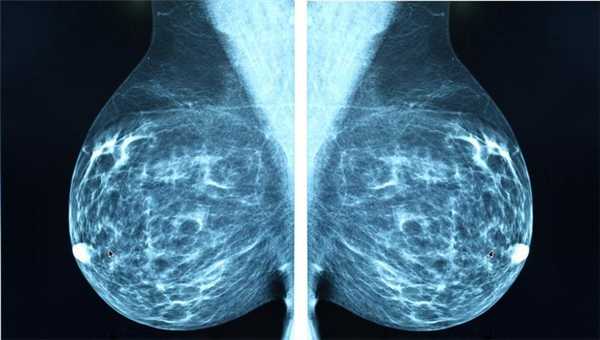

- рак молочной железы;

Маммография

Отдельный вид рентгенографии, разработанный для диагностики заболеваний молочной железы, поэтому проходят маммографию женщины. О рекомендуемом возрасте для проведения процедуры единого мнения нет. Маммография помогает убедиться в отсутствии злокачественной опухоли с точностью до 89%. Считается, что женщины должны проходить обследования регулярно, начиная с 39 лет, хотя некоторые онкологические сообщества рекомендуют обследоваться с более молодого возраста.

Маммографию назначают для диагностики рака молочной железы, процедура проходит быстро, это плюс, но пациентку облучают, а риск неверного диагноза остаётся, это минус. Маммография может быть цифровой и плёночной, цифровая маммография обеспечивает получение более чёткого снимка.

Классический рентген по-прежнему остаётся важным методом для диагностики самых разных заболеваний. Например, маммография (рентгеновское исследование молочных желез) - лучший способ скрининга рака молочной железы. Возможности КТ в выявлении злокачественных и воспалительных процессов в этом органе существенно ниже.